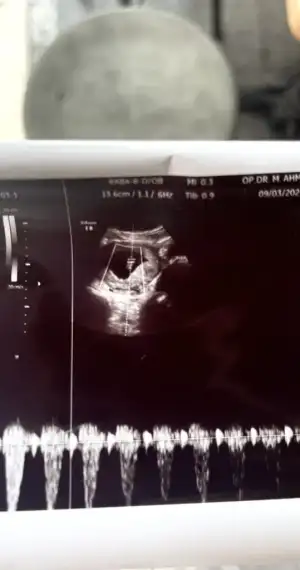

Kızlar az önce verdiğiniz bilgiye göre ph benim 6 yani kız

Ama ultrason koycam lütfen bi yorun yapın 😃

Aslında sana olan hissiyatım hep oğlun olacağı yönündeydi ama şimdi ultrason fotoğrafında kız gibi hissettim 🙈

Ya hahahahha valla yorum yapmaya çekiniyorum artık 😂😂 ama tutmuyor bende ne yapayım 🙈🙈 sadece oğlum hep kese de soldaydı o doğru çıktı bak ramzi'de 😅 bunda baktım ama e nabız da yok klinikte direk striple bakmışlardı. Ama bunda da ramzi teorisine göre kız, hissiyatım da kız bakalım 😂

Bebiş kesenin sağında mı solunda mı? Birde karından ultrason mu 😍 eğer karından ve kesenin sağındaysa kız, solundaysa erkek oluyor teoriye göre tabi ama hayırlısı 😍

Bunda da benim de her şey kızı gösteriyo, hissiyatım da çok kız olduğunu söylüyo ama bakalım, çok merak ediyorum cinsiyetleri 😍

Canım aaaaaynen bugüne kadar hep erkek hissediyordum ama bu ultrasonla bu kız dedim 🙏🏻🌸🌸🌸😳😃😃

Valla karından baktı ve karnımın sol tarafına koyunca cihazı görüntü netleniyordu bu ne demek??

Belki kese sola yakındır ama bebiş ne taraftaydı kesenin sağ mı sol mu onu tam anlayamadım resimden :)

Nub unu anlayamadim, nub a doktorlar bile çıkıyor diyorlar, ama sen görünce paralel gibimiydi nub u nasıldı?

Ay benimkinde sanki nubu da belli gibiydi paralel 🙈 anlayan bi arkadaşım nubu baya görünüyo paralel, kız büyük ihtimalle dedi dün bana 😁

Ya şu organ oluşan yeri oluyor heralde, o keseye paralelse kiz dikse erkek, ben 11. Haftada tanıdık bi doc var kadin dogumcu ona gideceğim, cinsiyeti soracağım bakalim tahmin yürütecek mi🤣çünkü gittiğim özel doktor 16. Haftada kesin olmadan demiyormus.

Çevirince anladım tamam kesenin sağında kız benceee 🤩

Evet kesenin sağında 😃

Bakalım kız tezini kim çürütecek kesenin sağındaydı benim oğlum diyerekten 🤣🤣🤣